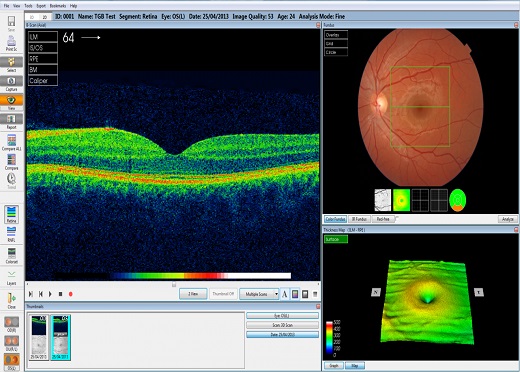

谱域光学相干断层扫描成像系统(SD-OCT)

苏州350vip浦京科技有限公司提供专业的光学相干断层扫描产品(OCT)相干产品及系统,提供产品有扫频源激光器、超宽带光源、扫描振镜、扫描相机、OCT光谱仪、信号采集与处理系统等